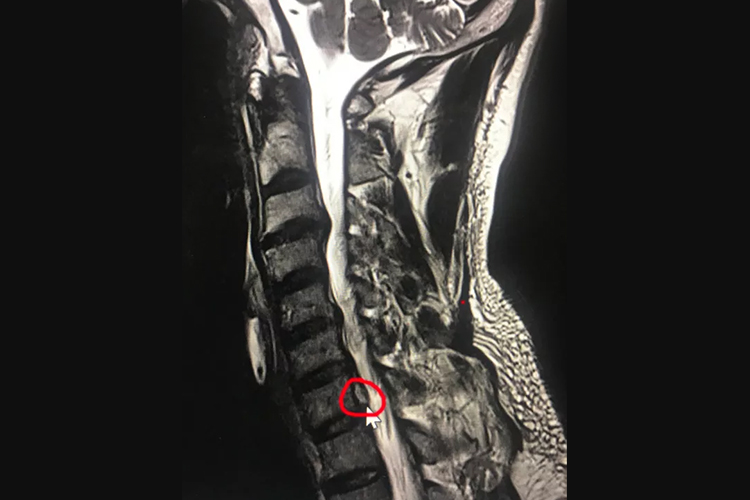

患者多表现为突然起病,可出现颈项痛、颈肩痛或上肢放射痛等表现,有时可感到上肢麻木、感觉减弱,严重时可感到下肢单侧发麻、行走困难。行颈椎MRI检查可见颈椎6-7椎间盘突出。